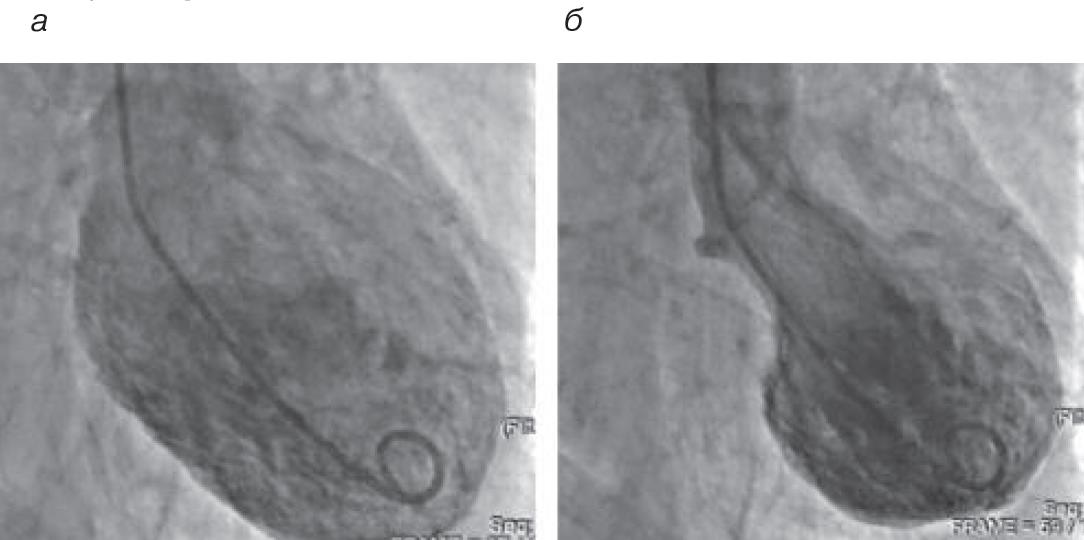

Учитывая клиническую картину, элевацию сегмента ST на ЭКГ, повышение уровня тропонина, пациентке установлен диагноз ишемической болезни сердца: инфаркт миокарда с подъемом сегмента ST. Через 30 мин после поступления экстренно выполнена коронаровентрикулография (КВГ): коронарные артерии без гемодинамически значимого стенозирования. По данным вентрикулографии – акинезия верхушки, перегородки и срединных сегментов всех стенок ЛЖ, гиперкинезия базальных отделов, фракция выброса (ФВ) –32% (рис. 2).

Рис. 2. КВГ: a – диастола; б – систола. Отмечается акинезия верхушки, верхушечных и срединных сегментов всех стенок ЛЖ, гиперкинезия базальных отделов ЛЖ.